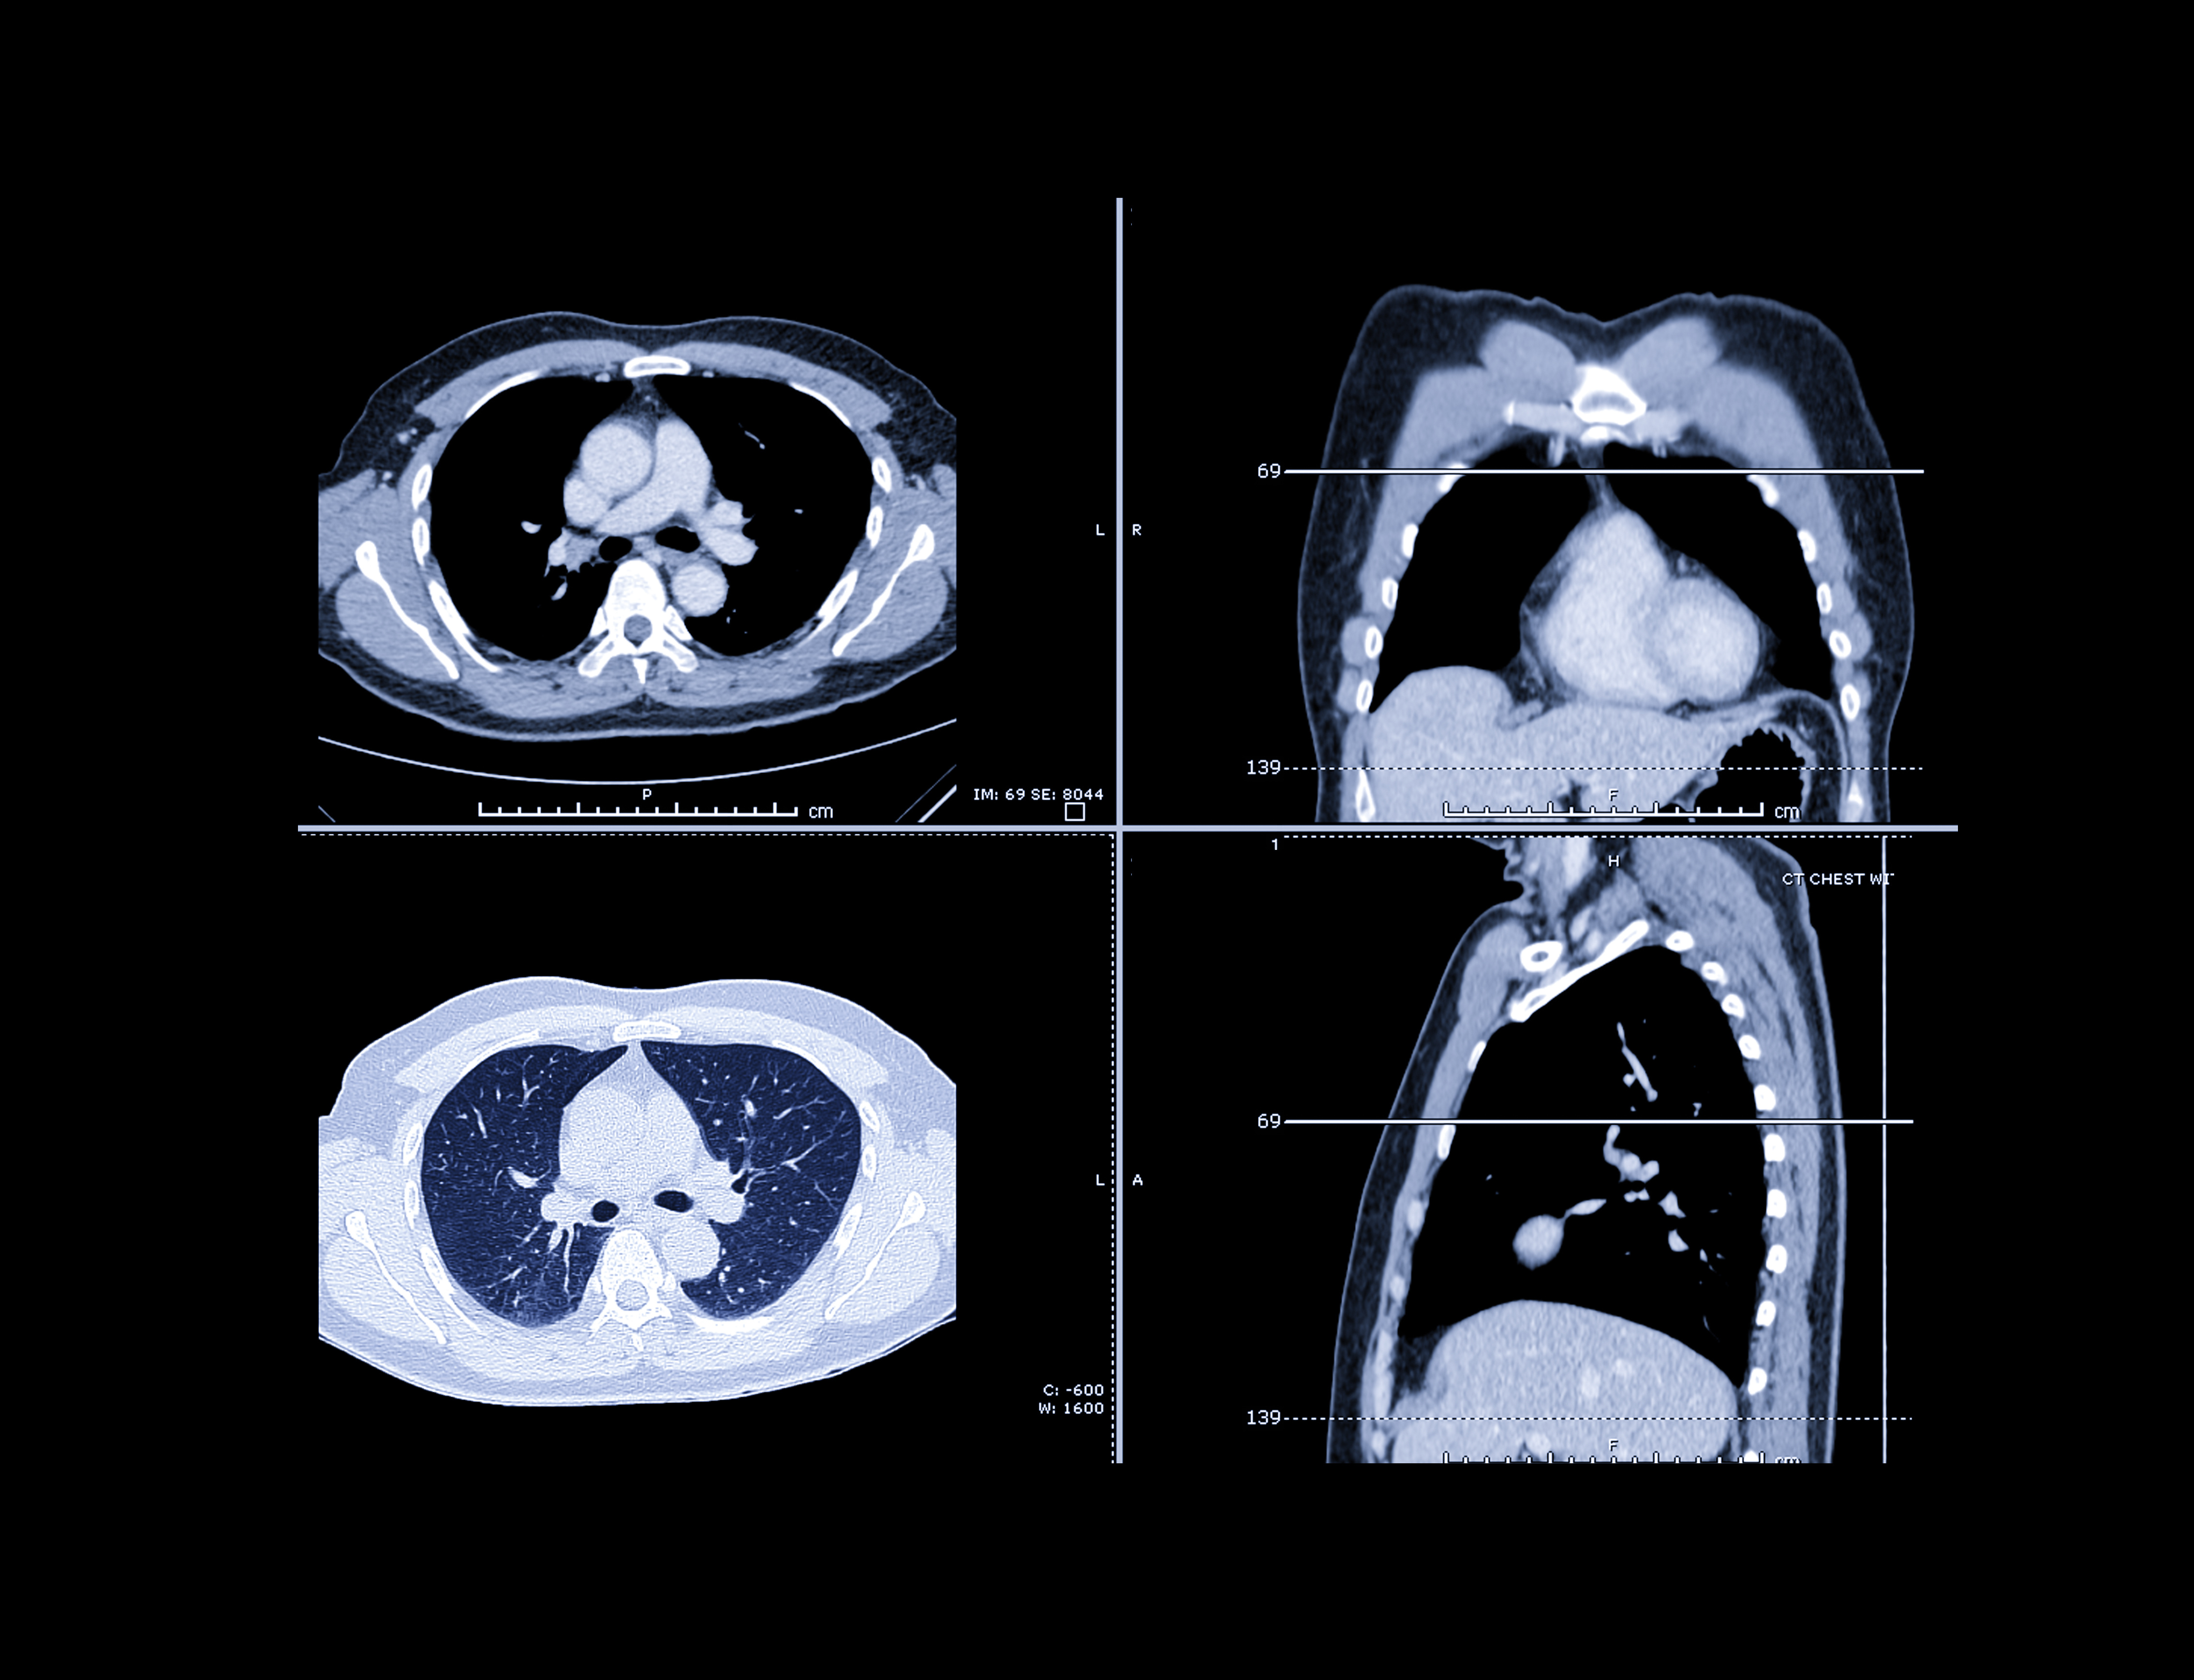

What is the diagnosis?